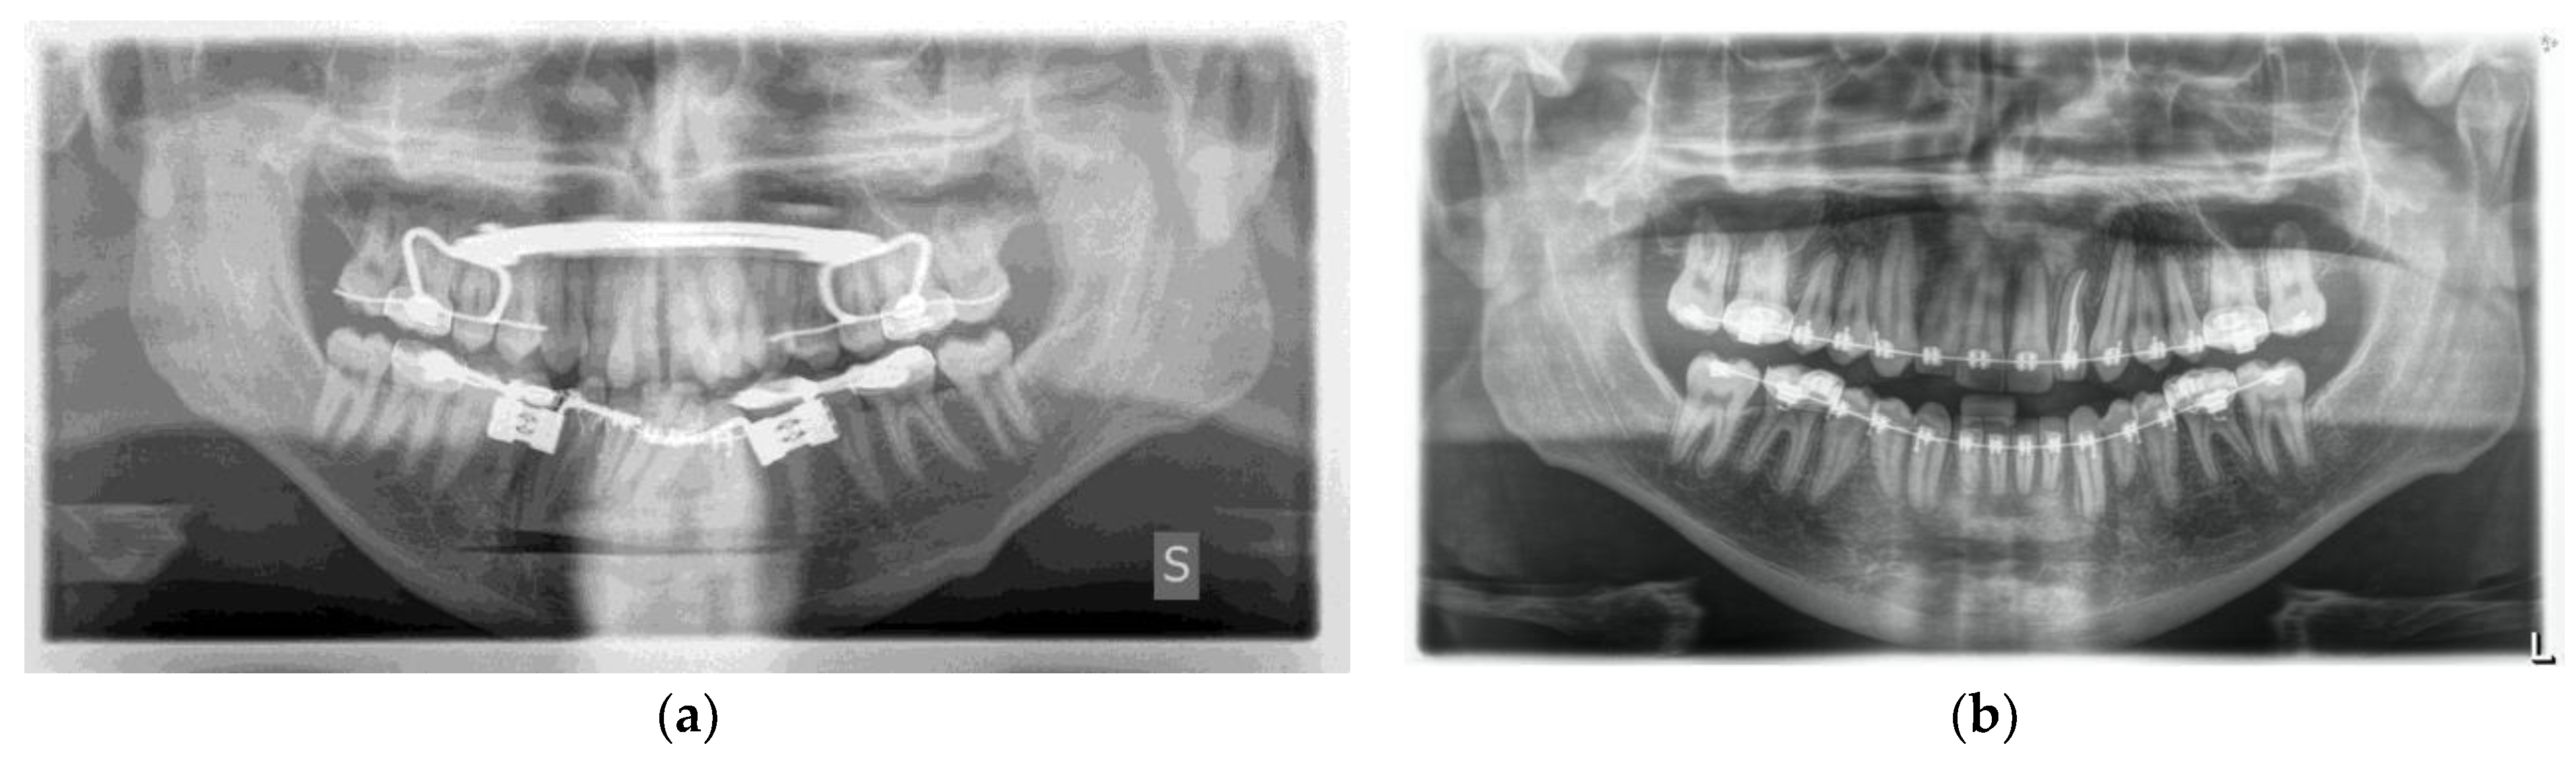

One week post-op, an OPT (Orthopantomography) X-ray was performed, which showed the adequacy of the osteotomy and the preservation of dental roots. Three years later, at the end of orthodontic alignment, the second surgical step was carried out (Figure 11a,b).

Figure 11.

(a) Postoperative Orthopantomography X-ray; (b) post orthodontic alignment.